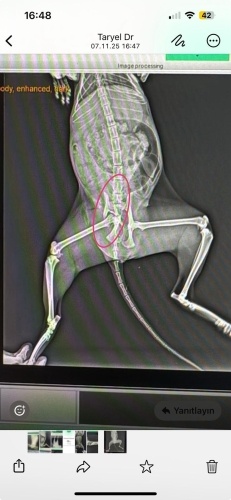

Kedinin röntgen fotosunu aşağıya attım, ben vet doktora gösterdim bana kediye araba güçlü şekilde çaemış dedi ve bir ayağı çalışamaz dedi tamamen kırılmış dedi sadece metal plak takabiliriz iyileşebilirde iyleşmeyebilirde diye söyledi (bu ameliyat metal plak yüzünden aşırı pahalı) başka bir seçenek çalışmayan bacağı ampute etmek. Kedi şu an yere yıöılmış ve haraket etmiyor yemek yemiyor bir tek günlerdir az az su içiyor ve altına yapıyor tuvaletini, yaptığı zaman yaraların üzeride bulaşıyor ve iyileşmesini önlüyor. Ne yapmam gerek kedinin ayağını ampute etseler böyle yaşayabilir mi? normal şekilde yemeğini yer suyunu içip azdan çoktan gezebilir mi? ağrısı hiç değilse azalsın istiyorum, gün günden eriyip gidiyor güzel hayvan.